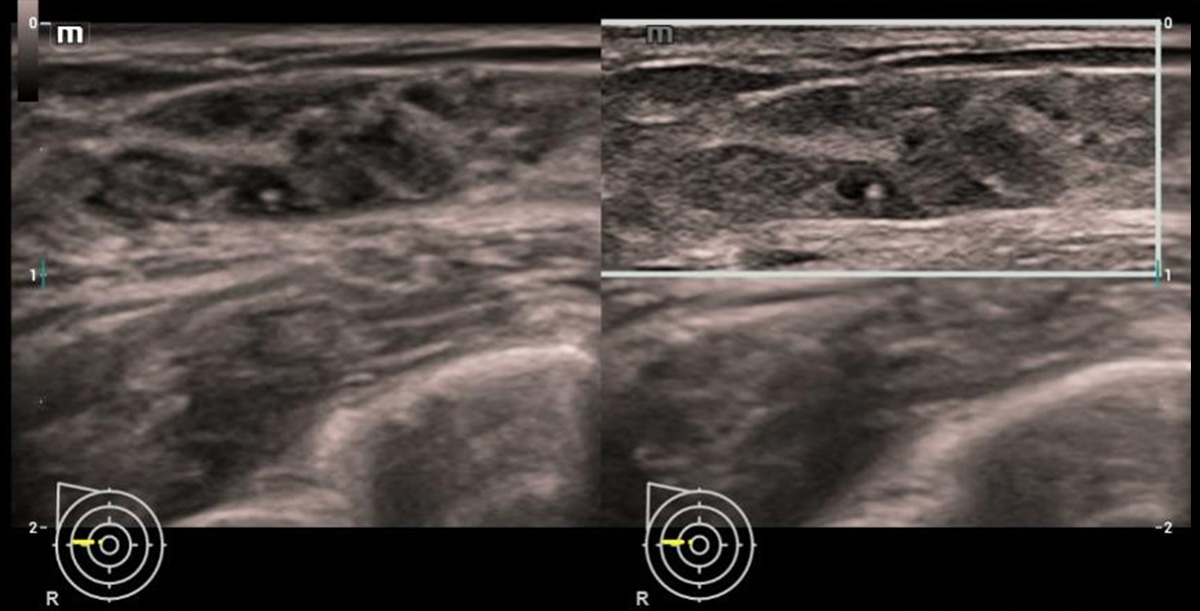

HD Scope

Verbeter de detailinformatie en het beeldcontrast op specifieke gebieden, vooral nuttig voor de weergave van de randen en de binnenstructuur

HD Scope

Smart Breast kwaadaardig

Smart Breast

Smart Breast is een analyse- en rapportagetool voor borstechografie om de klinische routine van borstechografie nauwkeuriger en productiever te maken. Het systematische beheer van meerdere laesies en de beoordeling van vier vlakken garandeert meer diagnostische informatie. Ondertussen verbetert de gestroomlijnde geautomatiseerde workflow de effici?ntie bij het scannen van borsten.